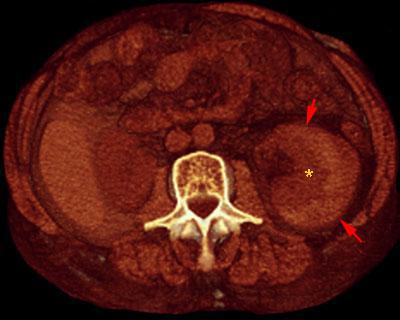

Hematoma subcapsular

VR seccional. Visión axial caudal. Serie no contrastada que muestra una colección hiperdensa (flechas) por fuera del parenquima renal (*), mas hipodenso, correspondiente a hematoma subcapsular